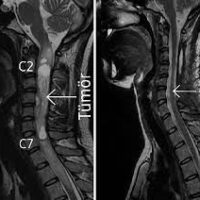

MR; omurganın primer tümörlerinin tanı ve değerlendirilmesinde tercih edilecek bir yöntemdir. Avantajları; yumuşak doku görüntülemesinin iyi olması, multiplanar görüntü elde edilebilmesi, nöral bası veya infiltrasyonun değerlendirilebilmesidir.